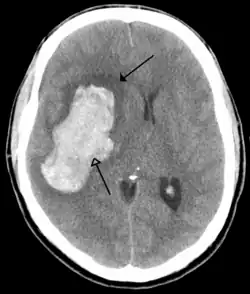

Tumours

Brain tumours can be either benign or cancerous. Most malignant tumours arise from another part of the body, most commonly from the lung, breast and skin.[178] Cancers of brain tissue can also occur, and originate from any tissue in and around the brain. Meningioma, cancer of the meninges around the brain, is more common than cancers of brain tissue.[178] Cancers within the brain may cause symptoms related to their size or position, with symptoms including headache and nausea, or the gradual development of focal symptoms such as gradual difficulty seeing, swallowing, talking, or as a change of mood.[178] Cancers are in general investigated through the use of CT scans and MRI scans. A variety of other tests including blood tests and lumbar puncture may be used to investigate for the cause of the cancer and evaluate the type and stage of the cancer.[178] The corticosteroid dexamethasone is often given to decrease the swelling of brain tissue around a tumour. Surgery may be considered, however given the complex nature of many tumours or based on tumour stage or type, radiotherapy or chemotherapy may be considered more suitable.[178]

Most strokes result from loss of blood supply, typically because of an embolus, rupture of a fatty plaque causing thrombus, or narrowing of small arteries. Strokes can also result from bleeding within the brain.[193] Transient ischaemic attacks (TIAs) are strokes in which symptoms resolve within 24 hours.[193] Investigation into the stroke will involve a medical examination (including a neurological examination) and the taking of a medical history, focusing on the duration of the symptoms and risk factors (including high blood pressure, atrial fibrillation, and smoking).[194] Further investigation is needed in younger patients.[195] An ECG and biotelemetry may be conducted to identify atrial fibrillation; an ultrasound can investigate narrowing of the carotid arteries; an echocardiogram can be used to look for clots within the heart, diseases of the heart valves or the presence of a patent foramen ovale.[195] Blood tests are routinely done as part of the workup including diabetes tests and a lipid profile.[195]

Some treatments for stroke are time-critical. These include clot dissolution or surgical removal of a clot for ischaemic strokes, and decompression for haemorrhagic strokes.[196][197] As stroke is time critical,[198] hospitals and even pre-hospital care of stroke involves expedited investigations – usually a CT scan to investigate for a haemorrhagic stroke and a CT or MR angiogram to evaluate arteries that supply the brain.[195] MRI scans, not as widely available, may be able to demonstrate the affected area of the brain more accurately, particularly with ischaemic stroke.[195]